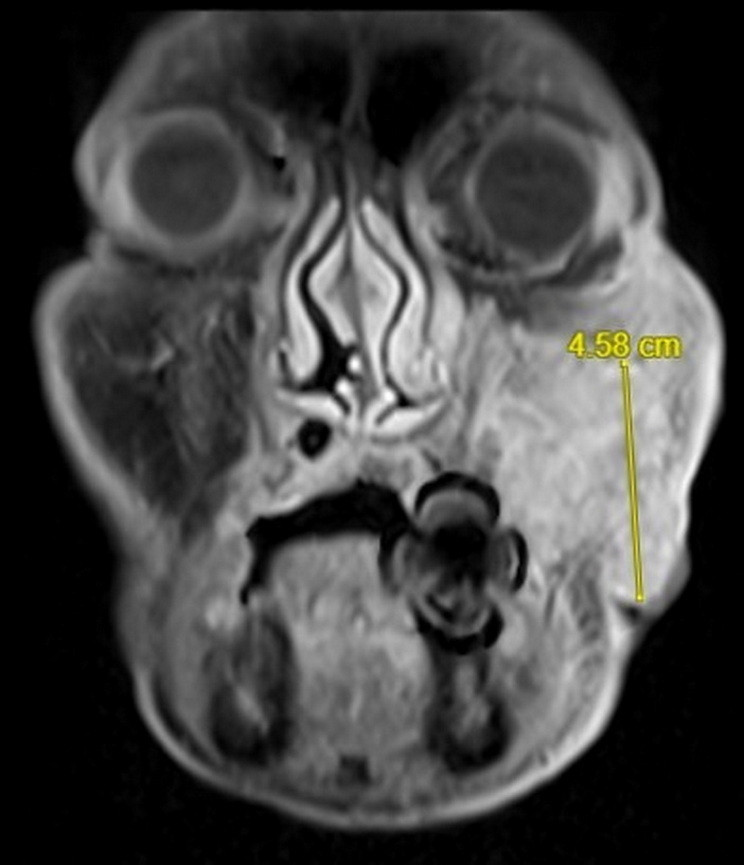

收治這名病患的彰基總院長陳穆寬表示,這名病患手術前的核磁共振顯示已是口腔癌末期(4期),腫瘤已經侵犯口腔、鼻竇及顏面皮膚,範圍已經達8公分,腫瘤範圍大,手術需要進行根治切除(包括半個口腔、鼻竇、及顏面)、頸部淋巴廓清術還有移植重建,手術治療過程耗時,對外觀影響也大。